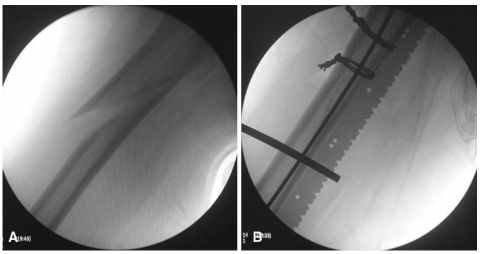

当骨折暴露时,一个钝的Hohmann牵引器可以放置在股骨的前部,抬高股外侧肌,第二个Hohmann牵引器可以放置在股骨的后部,抬高骨片。这样,骨折就显露出来,并且可以进行牵引和旋转调整来进行复位。获得良好的复位后可以用复位骨夹维持稳定(如图7a-d所示)。对于长斜形骨折碎片,可以使用钢丝或钢缆进行捆扎固定,我们使用一个过线器将钢丝从股骨的后侧通过到前侧,以避免损伤邻近的神经血管。我们更喜欢2毫米的钢丝,因为它更容易通过过线器绕过股骨(图8a,b)。如果没有钢丝过线器,应小心地将软组织从骨折断端中分离出来,并在外科医生的钳子帮助下将钢丝环绕股骨。拉紧钢丝时应采用拉-扭技术(pull-twist technique)。当钢丝固定时,建议在扩髓过程和最终插入髓内钉之前不要取下复位夹具,以避免钢丝发生断裂。髓内钉固定成功,静力锁定后,用生理盐水冲洗伤口,分层封闭。除非通过扩大的手术入路行切开复位,否则一般不需要留置引流管。

图8 A股骨粗隆下长斜形骨折;B双钢丝捆扎维持骨折复位